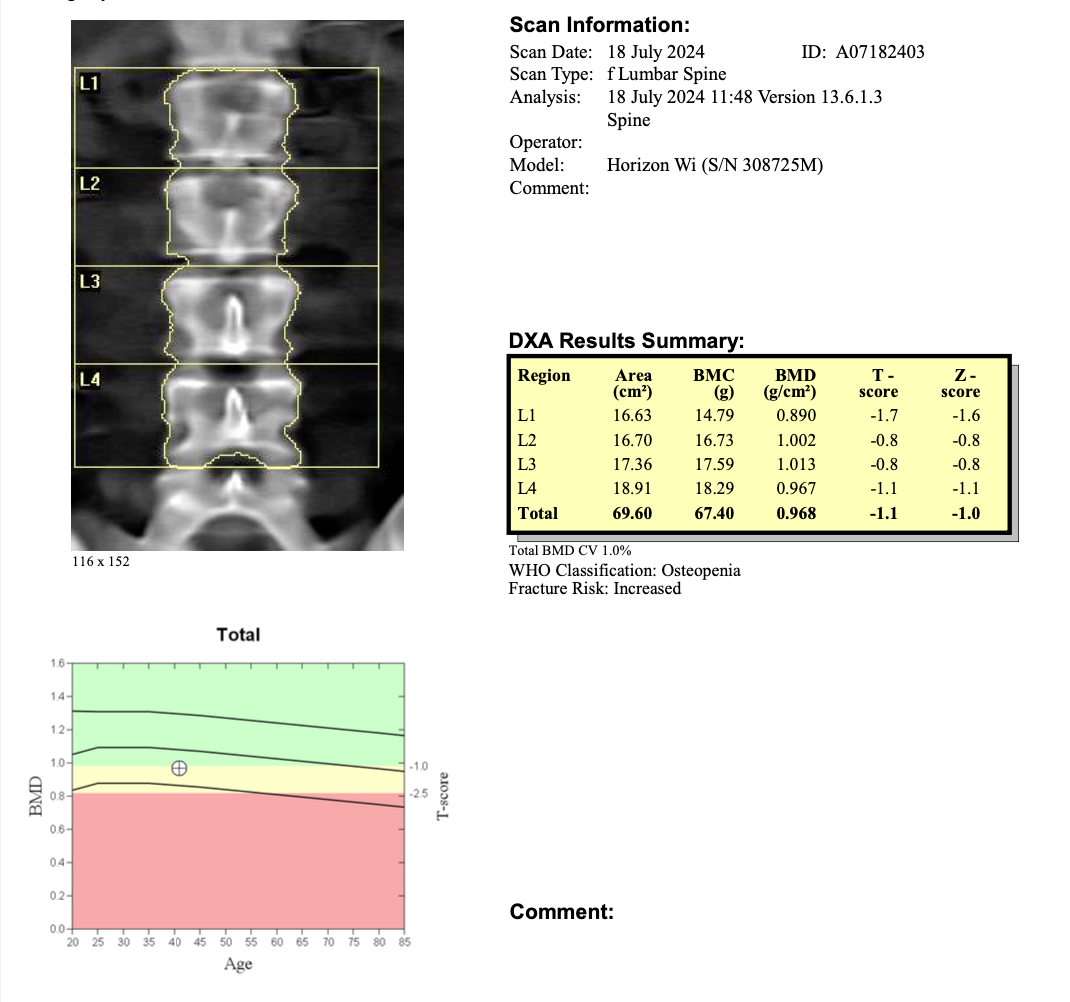

Example Report: